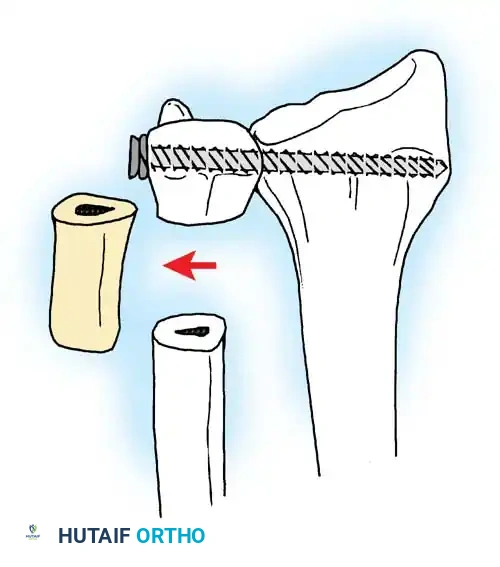

In chronic settings where the TFCC is irreparable, anatomic ligament reconstruction using a tendon autograft (e.g., palmaris longus) is indicated. The graft is routed through the distal radius and ulnar fovea to recreate the dorsal and volar radioulnar ligaments.

Tendon graft routing through osseous tunnels in the radius and ulna for anatomic reconstruction of the DRUJ ligaments.